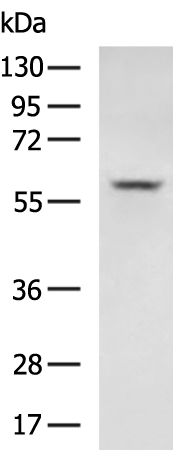

分类: 科研抗体货号: P05259别名: RPSKA; NY-CO-10; SDCCAG10; SDCCAG-10应用: WB,IHC反应种属: Human, Mouse, Rat